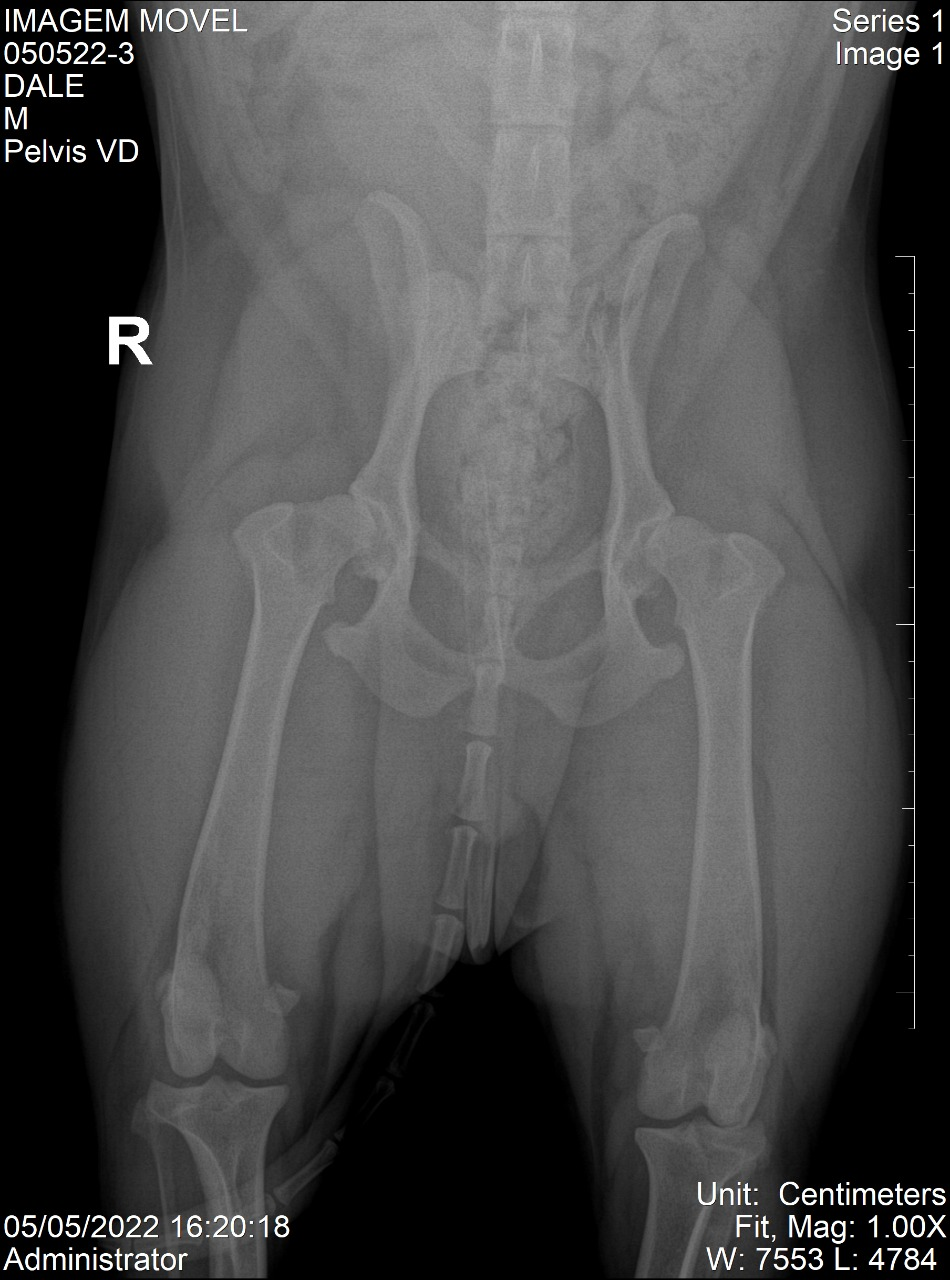

Ruptura de Ligamento Cruzado Cranial (RLCCd)

Histórico: Paciente com claudicação de elevação (não apoia o membro no chão) em membro pélvico direito.

O Exame: Projeção radiográfica mediolateral direita de joelho.

Desfecho: Sinais radiográficos compatíveis com RLCCd; Paciente encaminhado para procedimento cirúrgico e apresenta ótima recuperação post-op.